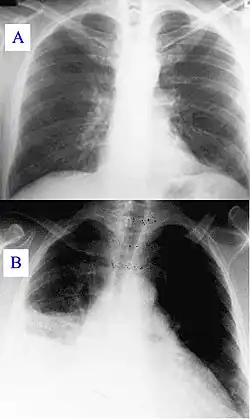

Chest X-Ray of a person infected by pneumonia

7. Chest X-rays: at least two serial x-rays showing sustained or worsening shadowing (infiltrates or consolidations)[15]